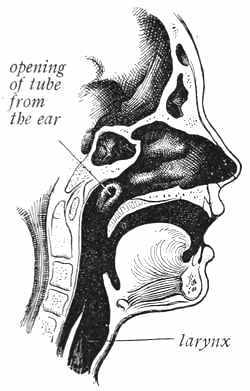

The cells in the skin of the nose secrete a watery fluid, and this fluid serves to moisten the air as it passes through the nose. Dry air irritates the mucous membrane which lines the nose, throat, and lungs, and it is very important that the air be moistened before it reaches the throat. Air is also warmed as it passes through the nose. Cold air is irritating to the throat and lungs. The small hairs in the nose catch the dust and dirt in the air and prevent it from going into the lungs.

The nose was made to breathe through, and all the air[49] that goes into your lungs should pass through your nose, in order that it may be moistened, warmed, and cleansed.

Frequently we see boys and girls breathing through the mouth. They do this because there is something in the nose that prevents the air from passing freely through it. If there were nothing in the way, the child would breathe through the nose instead of the mouth, because the natural way of breathing is through the nose.

The most common reason for mouth-breathing is the growth of small lumps in the throat just behind the nose. These little lumps are called adenoids. They are not natural, and should be taken out. We do not know why they grow in some children and not in others, but we do know that they should be taken out so that the child can breathe easily through the nose. Large tonsils also cause[50] boys and girls to breathe through the mouth. Tonsils that are large enough to cause the child to breathe through the mouth ought always to be taken out. Large tonsils and adenoids are often found in the same child.

When a child breathes through his mouth all the time, his face takes on a peculiar shape. His upper lip grows long, his lower jaw drops back, and his whole face looks flat. His voice has a peculiar sound, and he finds it very hard to keep up in his classes at school. Children with adenoids and large tonsils are always backward in their school work, and may become deaf if the adenoids and tonsils are not removed.

If you breathe through your mouth instead of through the nose, go to the doctor and let him see if you have adenoids or large tonsils; if you have, let him take them out. You cannot possibly grow into a strong, healthy man or woman if you have adenoids and do not have them removed.